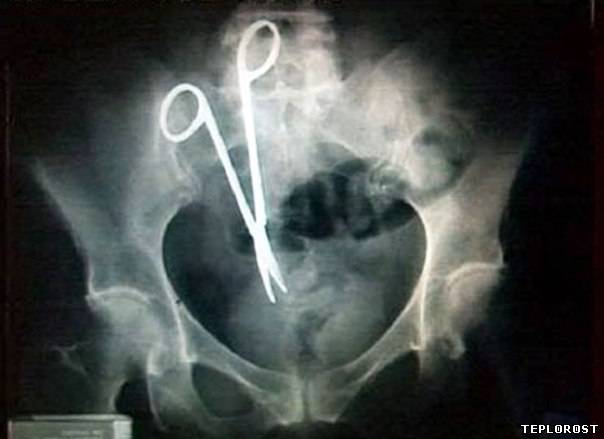

Забытые во время операции хирургические ножницы